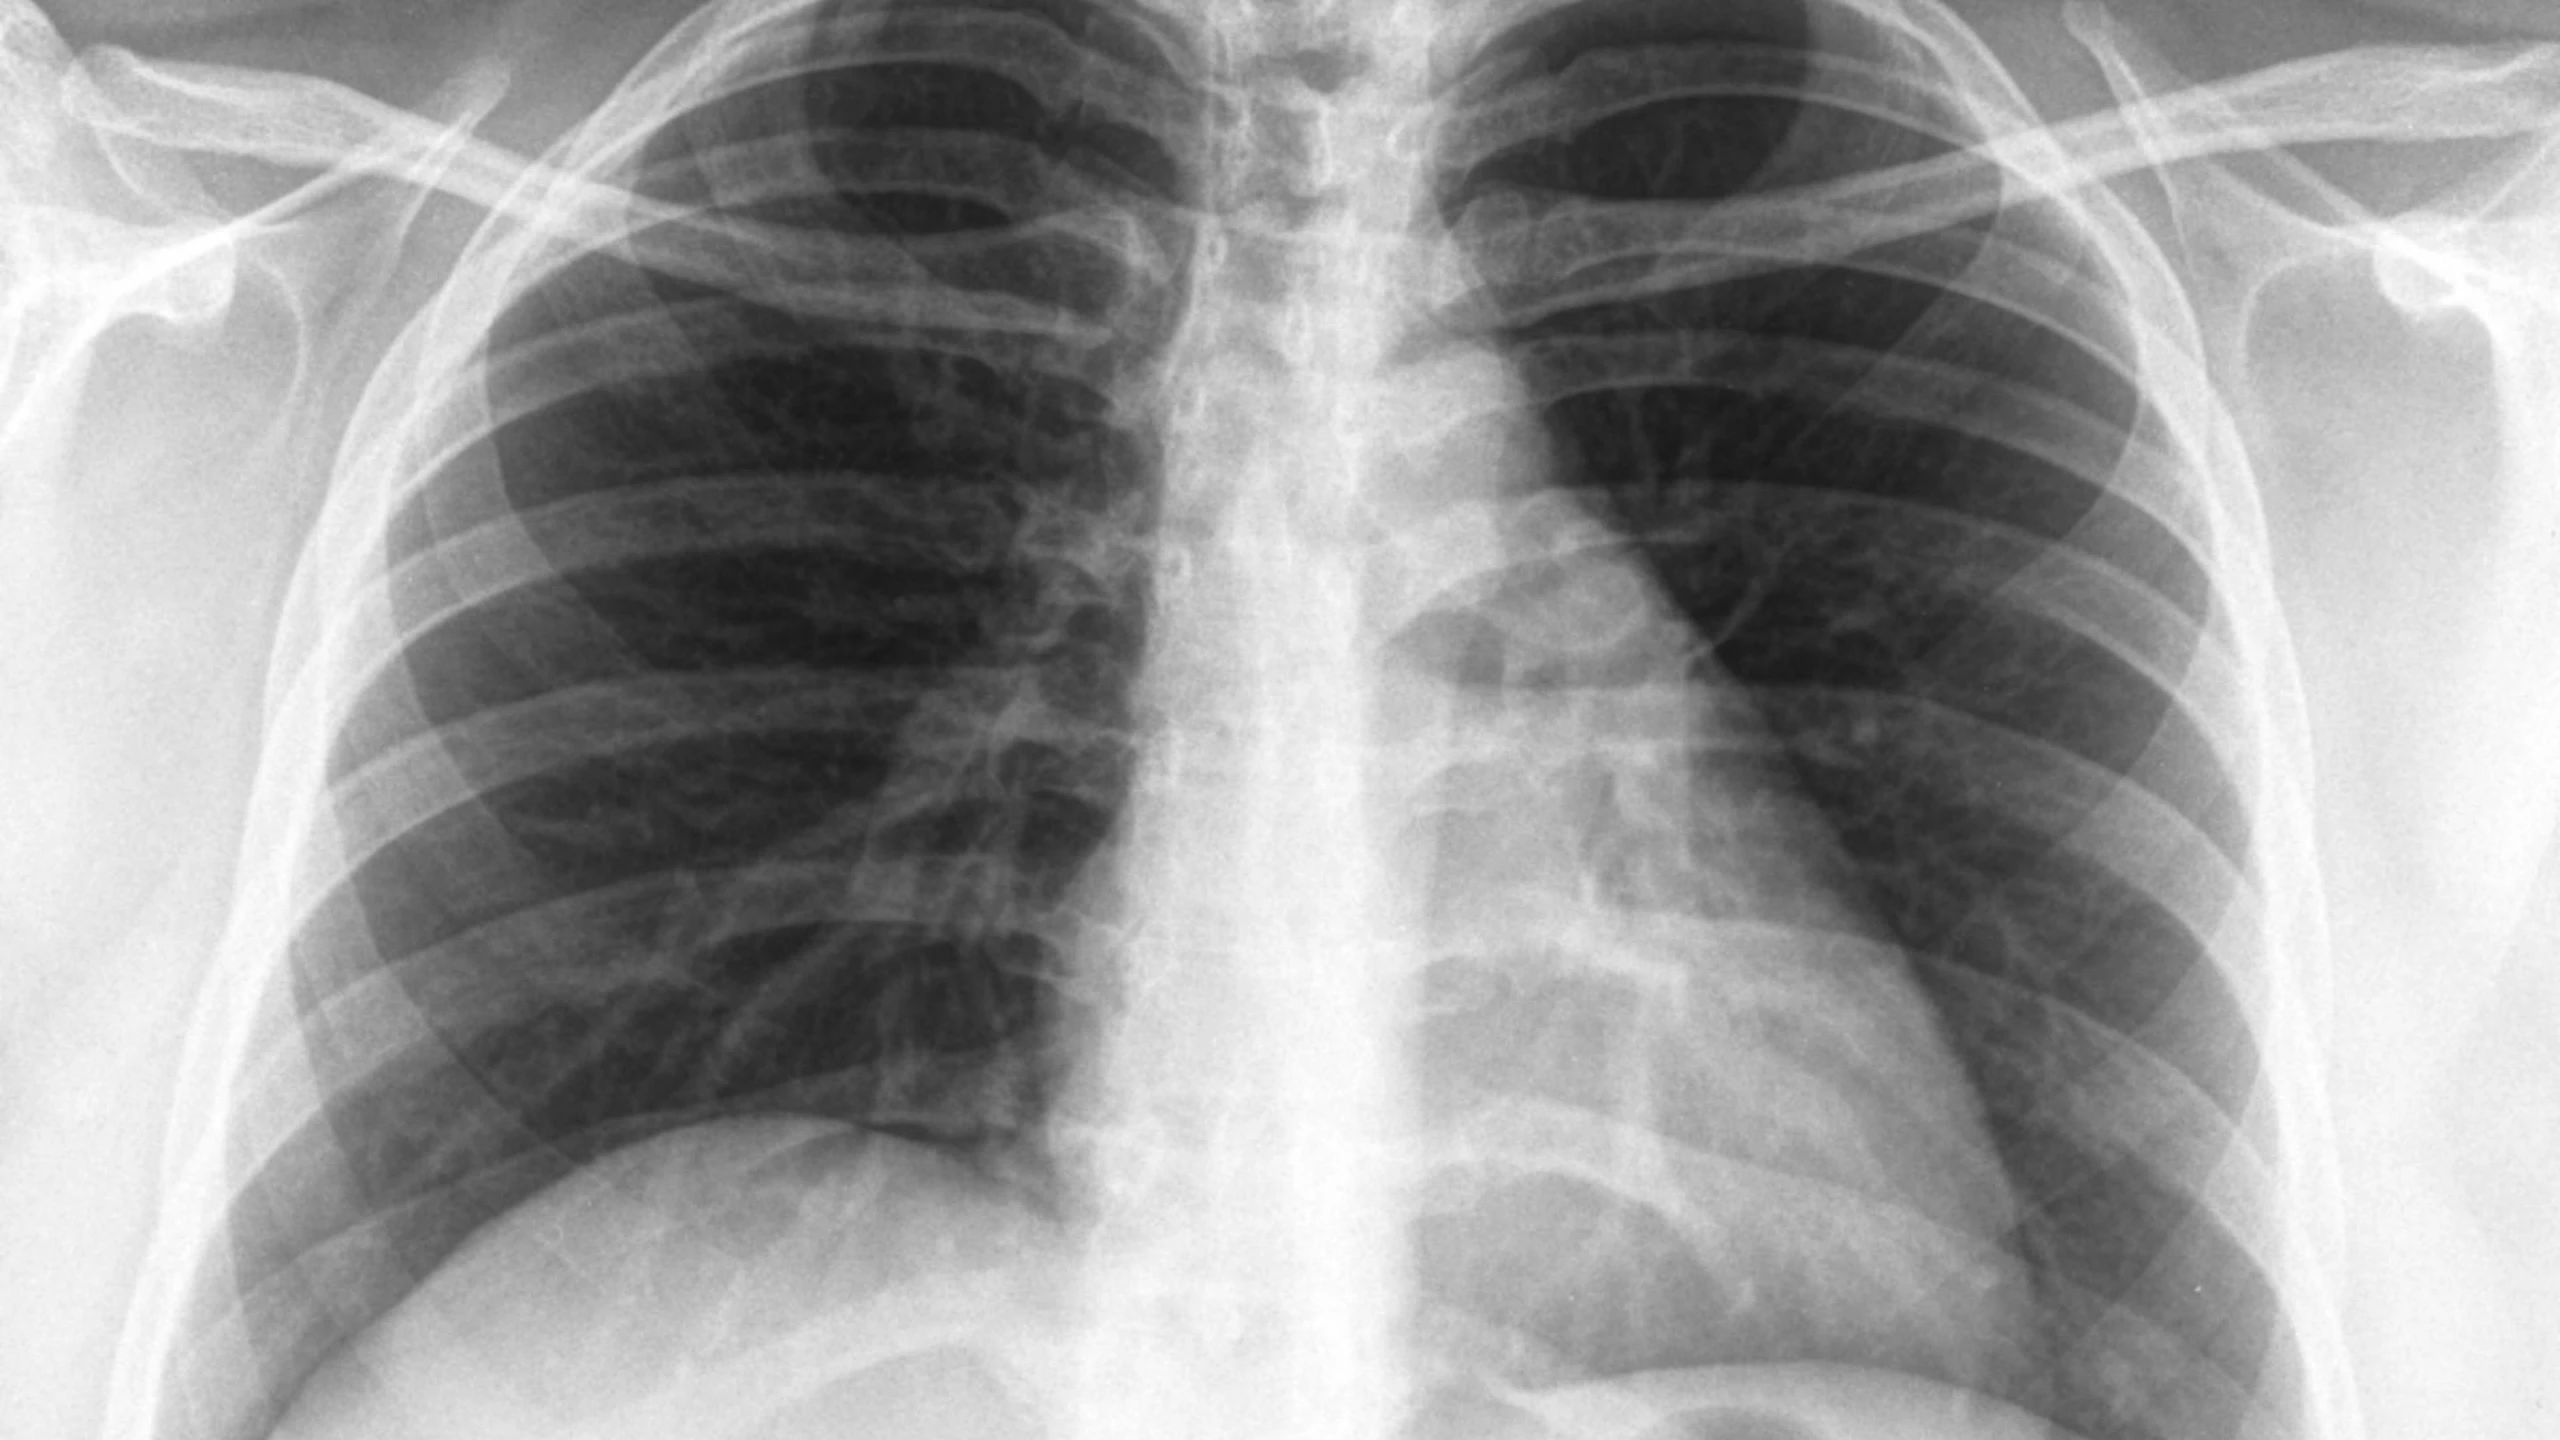

Viêm phổi bệnh viện (Hospital-acquired pneumonia – HAP), còn gọi là viêm phổi mắc phải trong bệnh viện, là một nhiễm khuẩn đường hô hấp dưới do vi khuẩn, xảy ra sau ít nhất 48 giờ kể từ khi nhập viện và không liên quan đến đặt nội khí quản lúc nhập viện. Người bệnh có thể xuất hiện nhiều triệu chứng như sốt, ớn lạnh, khó thở, đau ngực, và có nguy cơ cao gặp biến chứng nghiêm trọng thậm chí tử vong. Viêm phổi bệnh viện xảy ra phổ biến hơn ở người cao tuổi, người có sức khỏe yếu hoặc suy giảm miễn dịch. Bài viết này sẽ cung cấp các thông tin về nguyên nhân, triệu chứng, chẩn đoán và điều trị viêm phổi bệnh viện.